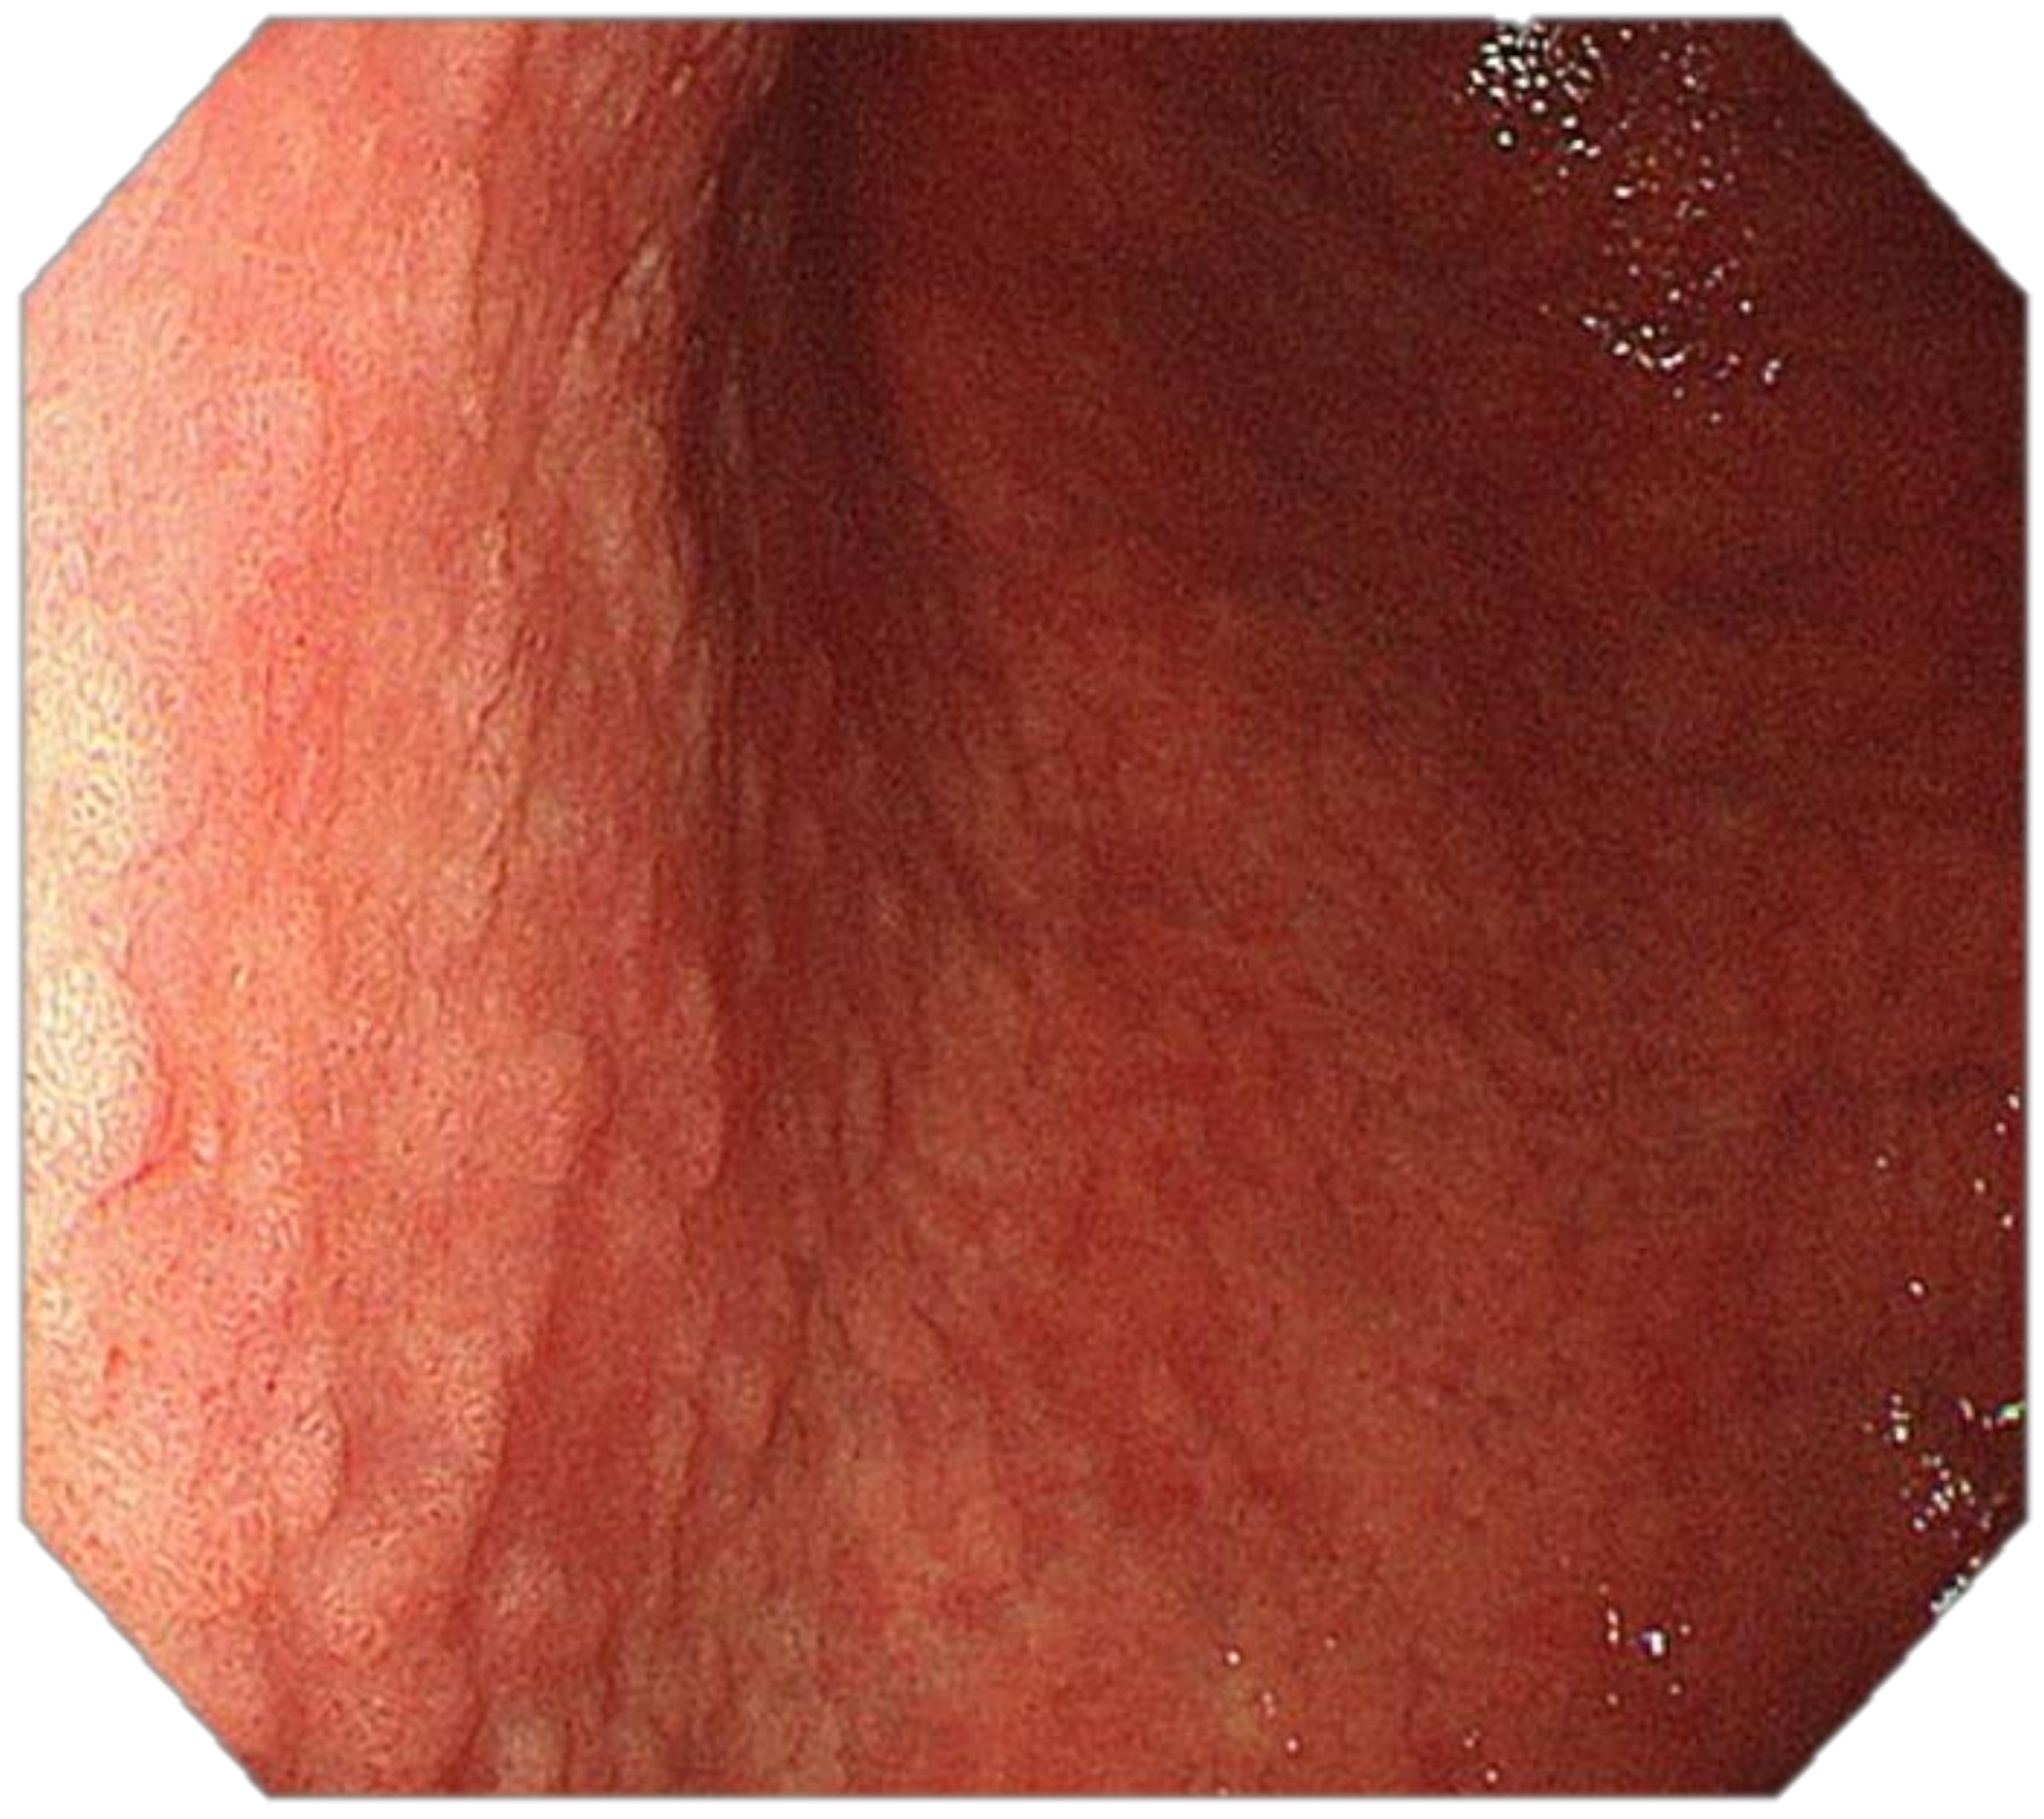

Optimal mucosal visualisation should be obtained through a combination of air insufflation, aspiration and the use of mucosal cleansing techniques with mucolytic and defoaming agents (e.g., N-acetylcysteine and simethicone) [157], see Figure 8, Figure 9, Figure 10, Figure 11, Figure 12, Figure 13, Figure 14. Despite progress made to date, premalignant lesions and early gastric cancer are still being missed [191,192]. A meta-analysis of 22 studies estimated a rate of missed gastric cancer at endoscopy of 9.4% [193]. Missed cancers were located mainly in the gastric body. Younger age (<55 years), female gender, marked gastric atrophy, gastric adenoma or ulcer, and inadequate number of biopsies were reported as predictive factors for diagnostic failure [193].

Our recommendation for daily routine practice is: (1) to use high-resolution white-light gastroscopes with magnifying NBI; (2) to achieve optimal mucosal visualisation with mucolytic and defoaming agents; (3) to keep minimal inspection time of 7 min.; (4) to obtain index images after a careful inspection (5) to take targeted biopsies of all suspicious or clearly pathological lesions; (6) to take multiple biopsies according to the protocol of the British Society of Gastroenterology (BSG) if suspicion of gastric atrophy and/or gastric intestinal metaplasia arise [113].